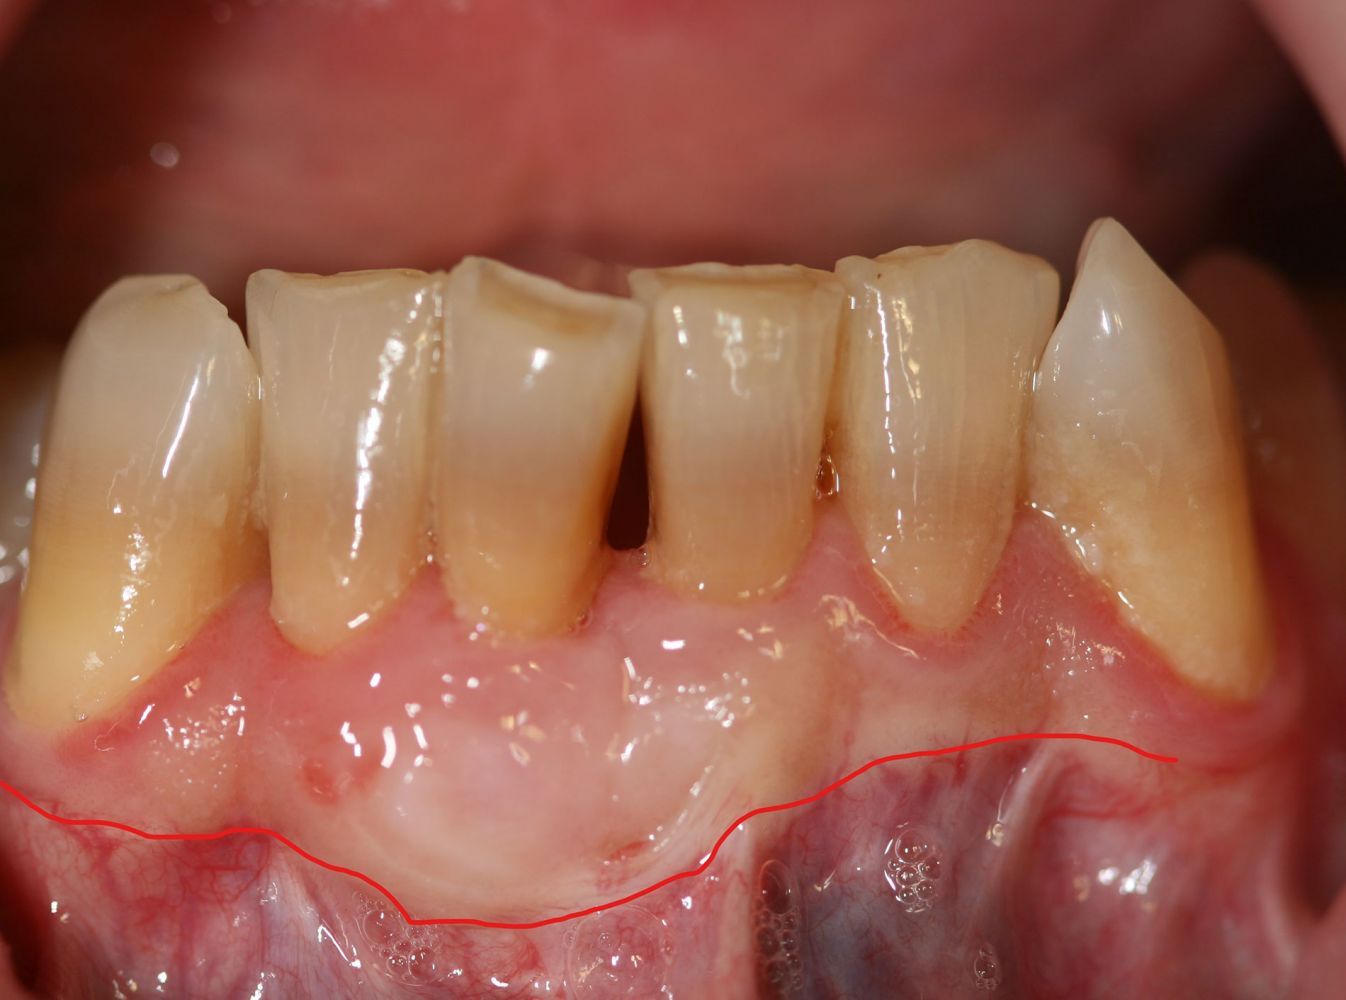

Caso de cirugía periodontal

Cirugía periodontal en un paciente